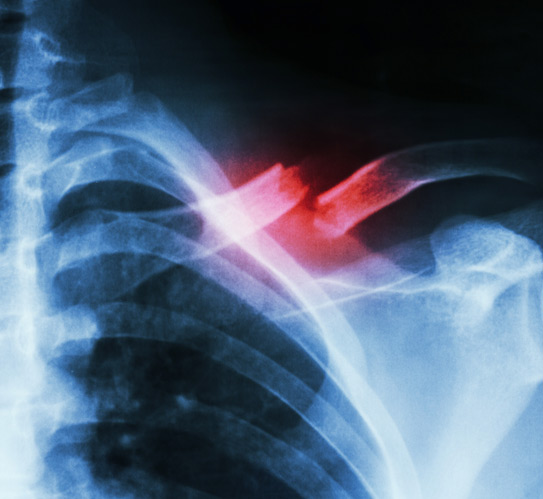

X-ray-showing-a-fracture-in-middle-left-clavicle

Although many shoulder procedures can be performed arthroscopically, some situations require an open surgical approach. Open surgery allows direct access to the damaged area, which may be necessary for large tears, complex fractures, or advanced joint deterioration. Incisions are typically a few inches long, and surgeons may use this method to ensure a more accurate repair. Patients should monitor for signs of infection, increased swelling, or unusual numbness after surgery and report concerns promptly to their provider.